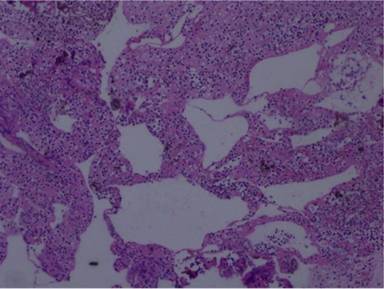

Cytology smears were cellular, and showed polymorphous, predominantly small, mature lymphoid cells, in a background of proteinaceous material (Figures 3 and 4). Mucin and epithelial cells were absent. Cell-block preparation of paraffin-embedded aspirate showed cystic spaces and dilated lymphatic channels, lined by a single layer of benign flattened endothelial cells (Figure 5). Abundant mature polymorphic leukocyte common antigen (LCA) positive lymphocytes were seen between these spaces (Figure 6). Immunohistochemical studies were also carried out for CD20 (B cell marker) and CD3 (T cell marker), and an intermixed population of B and T cells were found. The diagnosis based on EUS-FNA was pancreatic tail cystic lymphangioma.

Figure 5. Cell-block preparation of paraffin-embedded aspirate fluid, showing cystic spaces and dilated lymphatic channels lined by endothelial cells. Abundant polymorphic mature lymphocytes are seen between these spaces (200x, H&E stain). |